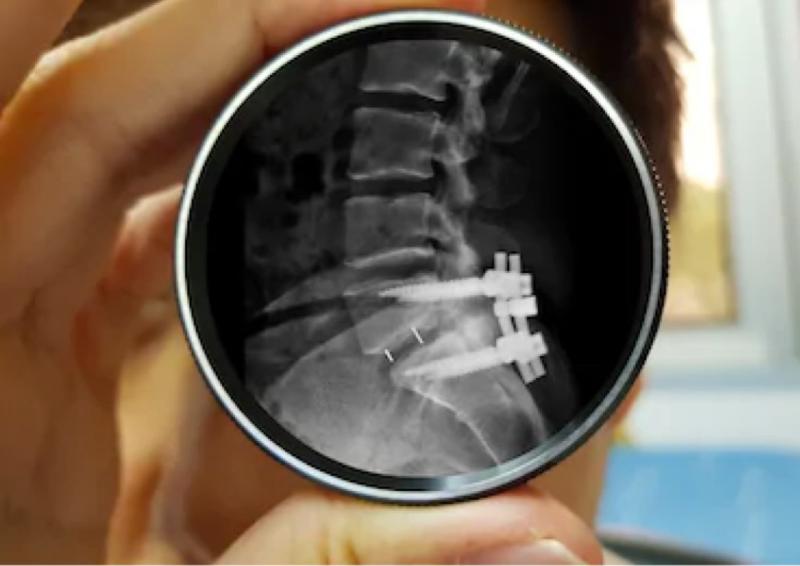

Spinal Fusion

In more serious situations, spinal fusion can be required. This surgery involves joining two or more vertebrae together to stabilize the spine and prevent further narrowing of the spinal canal. While spinal fusion can limit mobility, it can also provide long-term relief from pain and prevent the condition from worsening.